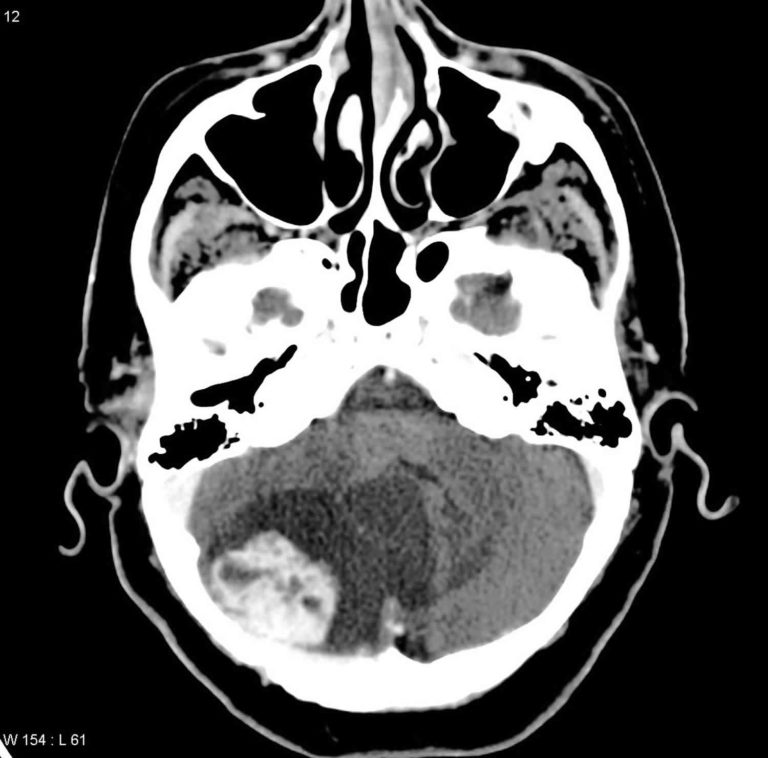

Multicystic hemangioma. CT imaging shows a HH with a complex mass What Does A Hemangioma Look Like hemangiomas, also known as strawberry marks, are benign tumors of blood vessels, most commonly seen in children. hemangiomas of the skin usually appear as small red scratches or bumps. a hemangioma or haemangioma is a usually benign vascular tumor derived from blood vessel cell types. hemangiomas look like reddish, purplish, raised, bumpy lesions on the skin.. What Does A Hemangioma Look Like.